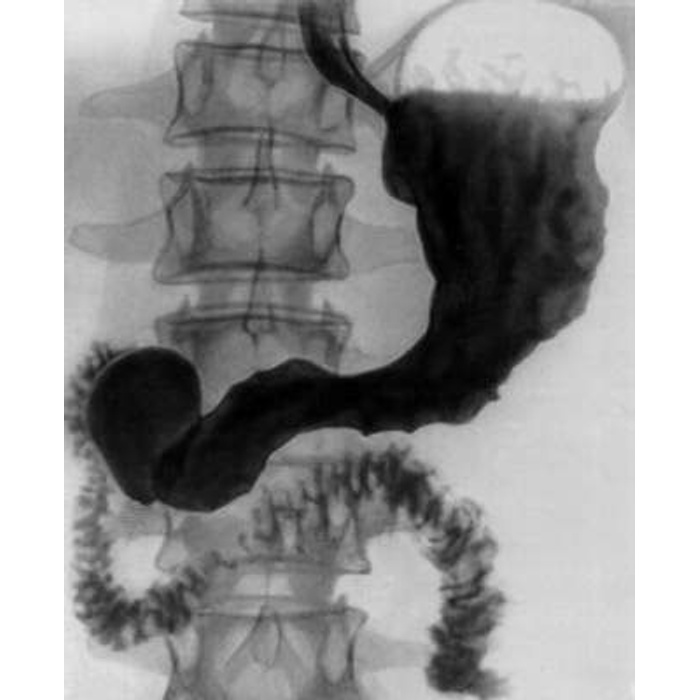

Современные технологии в медицине: рентгенодиагностика заболеваний желудка

Раздел: Фотогалерея мыслей